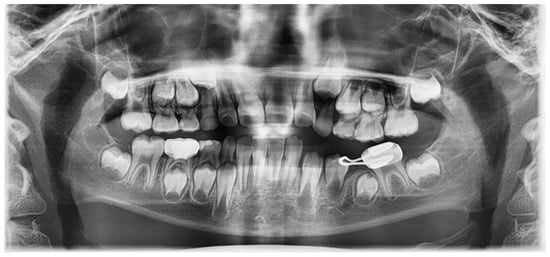

Six months after treatment, the cyst size was significantly reduced, and the premolars had erupted (Figure 5). Thirty months after treatment, the extruded canal filling material remained around the roots of the erupted left mandibular premolars (Figure 6). The patient showed no clinical symptoms.

Figure 5.

Six months after marsupialization: (a) periapical radiograph; (b) intraoral photo. Left mandibular premolars have erupted and extruded canal filling materials still exist.

Figure 6.

Thirty months after marsupialization. Panoramic radiograph. The extruded canal filling materials remain around the root of the erupted left mandibular premolar.